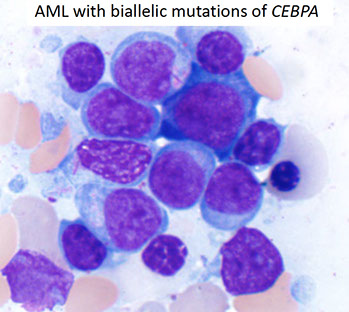

- Acute myeloid leukemia with biallelic mutation of CEBPA